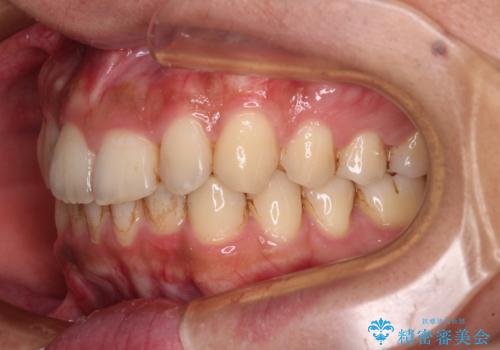

前歯のデコボコをスッキリ改善 インビザライン矯正

- 上下前歯のデコボコを気にして来院された患者様です。

全体的に叢生は軽度であったため、インビザラインにて矯正治療を行うこととしました。

デコボコの改善はもちろん、下顎前歯が隠れてしまうディープバイトも一緒に改善することができ、奥歯への負担を軽減することができました。